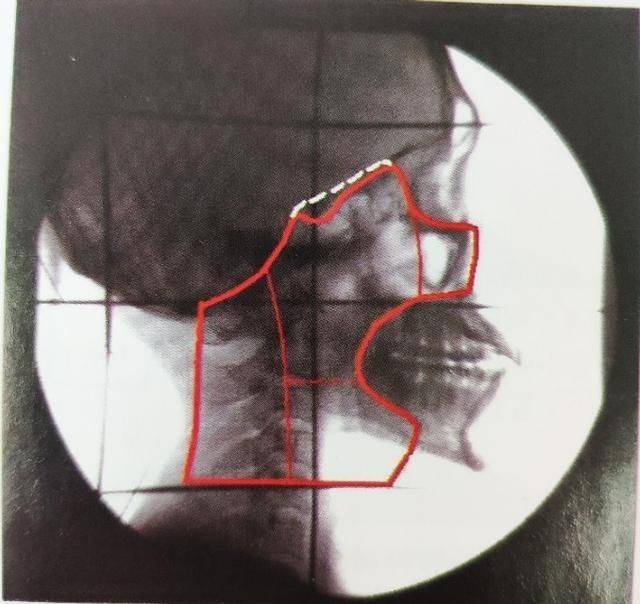

不仅仅是有鼻咽癌家族史的人群,携带EB病毒高危亚型的高危人群,也可以定期进行鼻咽癌筛查,如血液中EB病毒抗体、鼻咽纤维镜和头颈MRI检查,提高鼻咽癌早诊率,从而治愈鼻咽癌,实现疾病的二级预防。